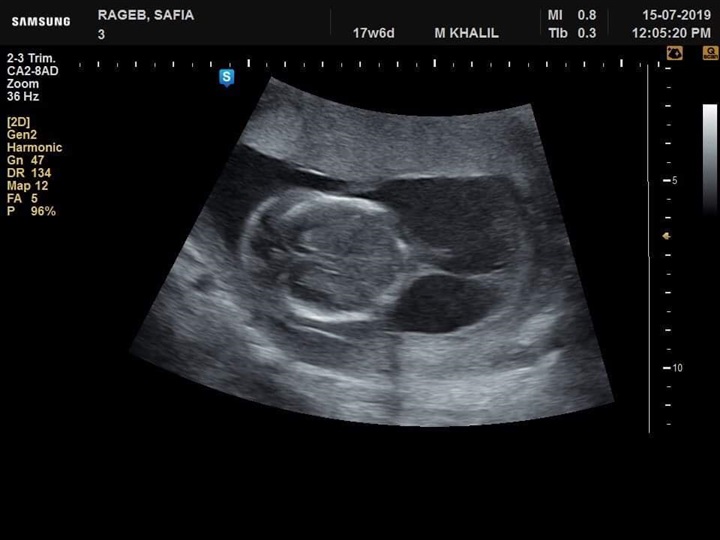

نجح فريق طبي من قسم النساء والتوليد في مستشفى جامعة كفر الشيخ في تشخيص  حالة تم تحويلها إلي مستشفي الجامعة بسبب وجود زيادة في السائل الامنيوسي، وبعد توقيع الكشف وتصوير للجنين تفصيليا تم اكتشاف وتشخيص جنين داخل رحم أمه وبه انسداد المرئ ووجود ناصور بين القصبة الهوائية والمرئ

عدم تكوين الجسم الثفني الذي يصل فصي المخ سويا وجود تشوه في القدم وابتعاد ألاصبع الكبير للقدم عن الإصبع الآخر وزيادة في السائل الامنيوسي تم بذل لتر و ٨٠٠ سم من السائل الأمنيوسي وإرسال بعضه للتحليل الكروموسومي.

وأوضح الفريق الطبي في قسم النساء والتوليد بمستشفى جامعة كفرالشيخ برئاسة الأستاذ الدكتور محمد خليل أنه تم تشخيص حالة أخري استسقاء لجنين داخل الرحم لأسباب جينية وحالة أخري بضمور كليتي الجنين وهذا التشخيص المبكر يساعد علي مساعدة الجنين الأول بعمل عملية له بعد الولادة لإصلاح الانسداد بالمرئ وإصلاح الناصور أما في الحالتين الثانيتين فينصح بعدم تعرض الأم لعمل عملية قيصرية في مثل هذه الحالات.